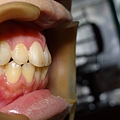

先拔除單側上顎,因牙根無位置生長,所以牙根聚合且彎曲。 傷口恢復良好。

患者再接再勵,將上顎另一側智齒也拔除。 接著下顎也安排時間取出。 目前傷口已完全復原。 |